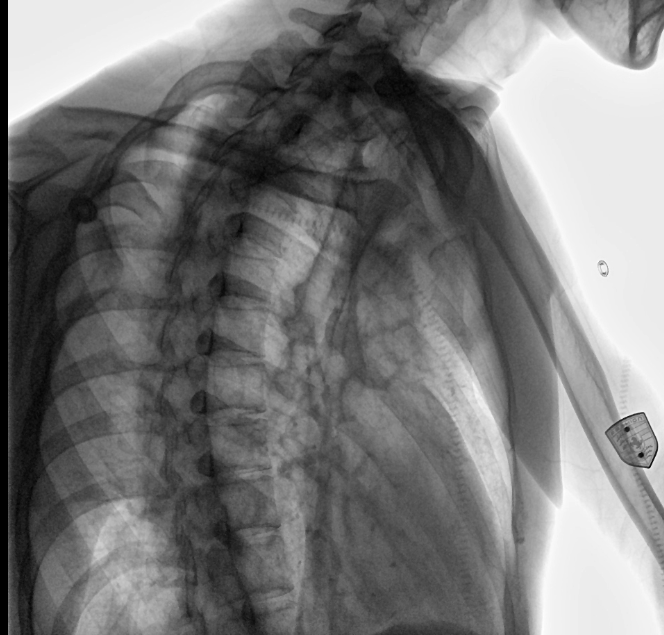

位于衡水市中醫(yī)醫(yī)院的動(dòng)態(tài)平板數(shù)字化X射線系統(tǒng)DTP571具備高速高清點(diǎn)片功能。這是一款對(duì)放射科十分友好的產(chǎn)品。因?yàn)樗迅咚俸透咔妩c(diǎn)片結(jié)合,既能方便影像技師有效地抓拍需要的病灶的影像,又能給予影像醫(yī)生清晰的影像進(jìn)行診斷。